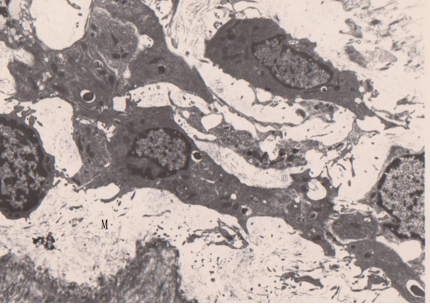

图-4. 组织通道透射电镜图像(X 12000):白种小猪的后肢膝关节内侧近骨侧的组织电镜图像显示细胞间隙大小不等,形状各异,间隙内充有质浆,及不同类型的细胞。均为无壁的经络间隙(M)。

图-5.鼠的舌部水肿组织透射电镜图像:显示组织通道与毛细淋巴管(L)紧密相接,毛细淋巴管有数个开放、端对端、及交搭重叠链接(J),经络通道(M)相互通连,经络液充满于各经络组织通道中。可以看到毛细淋巴管的开放连接处有大分子物质正在通过开放链接,开放连接处大分子物质与质浆蛋白集聚。